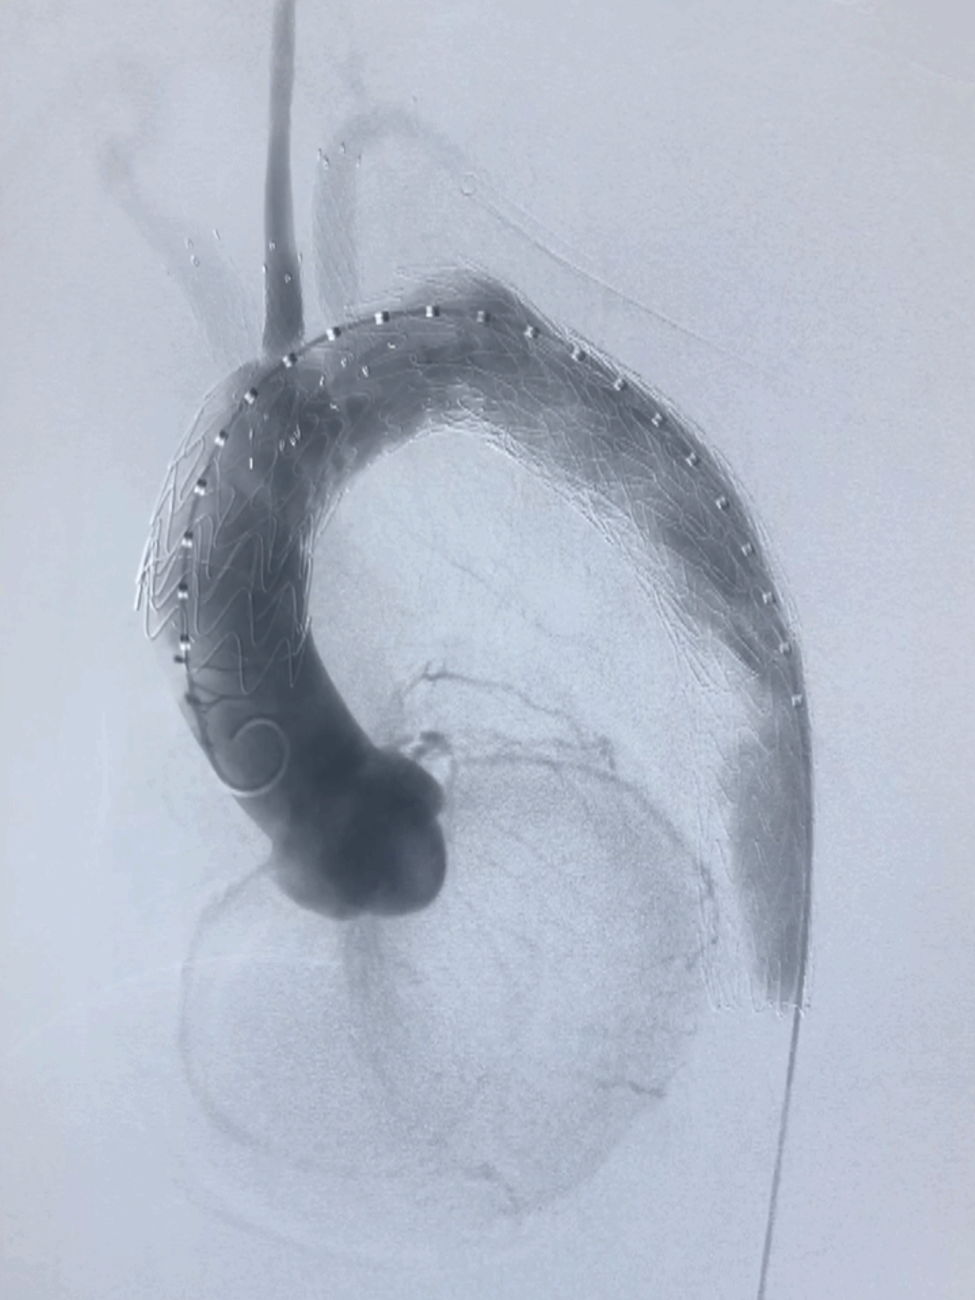

临床应用:医源性夹层:Castor分支支架+迷走右锁骨下动脉原位开窗(需90度角度配合特殊导丝完成)

逆撕A型夹层:Castor分支支架联合迷走左椎动脉预开窗。

弓部动脉瘤:Castor联合内嵌分支LSA预开窗术,目的为防内漏

避免转流的复杂病例:Castor+原位及预开窗(免转流三开窗)治疗弓部动脉瘤